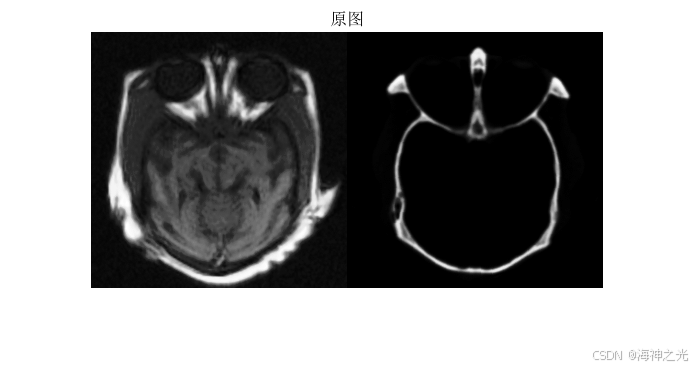

⛄一、同步各向异性扩散模型的MRI和CT医学图像融合

各向异性扩散模型(Anisotropic Diffusion)基于偏微分方程(PDE),通过控制扩散系数保留图像边缘信息,同时平滑噪声。在MRI和CT图像融合中,该模型利用两种模态的互补性:MRI提供软组织的高对比度信息,CT显示骨骼等硬组织结构。同步扩散的核心是通过联合扩散方程,在迭代过程中保持两类图像的结构一致性。

2 医学图像融合流程

对MRI和CT图像进行配准,确保空间对齐。采用线性或非线性变换(如B样条、Demons算法)消除模态间的几何差异。直方图匹配或归一化处理可减少强度分布差异。

多尺度分解

使用同步各向异性扩散模型对两幅图像进行多尺度分解。通过迭代求解扩散方程,生成基带(低频)和细节带(高频)分量。基带包含全局结构,细节带保留边缘和纹理。

⛄三、运行结果